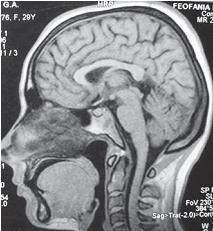

Известно, что болезнь легче предупредить, чем лечить. Что такое боль? Это, в первую очередь, сигнал о том, что в организме происходят неполадки. Постоянные хронические боли — это уже сигнал о серьёзных проблемах в организме, поэтому надо не только уметь слышать свой организм, но и оперативно реагировать на его сигналы. Боль в шее — ощущение не из приятных. Это вам скажет любой человек, испытавший её. Чтобы понять причину происхождения боли и установить точный диагноз, необходимо, в первую очередь, провести обследование, поскольку боли могут быть похожие, а вот причины их происхождения, как мы уже смогли убедиться, разные, следовательно и лечение разное. С заболеваниями позвоночника вообще желательно не затягивать, а своевременно обращаться к специалистам. Профилактика заболеваний позвоночника в любом случае не помешает, а вот самолечение без соответствующих знаний может и навредить. Как известно, шейный отдел позвоночника обильно снабжён сосудами, нервами. Пока позвоночник относительно «здоров» и имеет нормальный лордоз и «рабочее» состояние межпозвонковых дисков, то с сосудами, нервами, как правило, всё в порядке, то есть всё функционирует в естественном режиме. При прогрессировании дегенеративно-дистрофического процесса физиологический лордоз изменяется, что приводит к соответствующим проблемам. Для более предметного понимания сути вопроса предлагаю ознакомиться с рядом снимков МРТ шейного отдела позвоночника разных людей в качестве своеобразного визуального пособия и провести соответствующие самостоятельные сравнения состояния шейного отдела у данных пациентов. МРТ № 46 ![]() Возьмём за вариант нормы данный снимок МРТ № 46, на котором наблюдается нормально выраженный лордоз, высота межпозвонковых дисков, ширина позвоночного канала. Самое главное — отсутствие стеноза (сужения). Спинной мозг: контуры ровные, чёткие, структура гомогенная (греч. homogees — однородный), расположен почти в центре позвоночного канала и имеет нормальную толщину. Участков его патологического расширения или сужения не наблюдается. Ликворные пути свободны, проходимы.